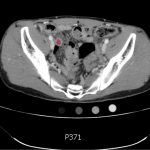

The CT abdomen/pelvis with intravenous contrast shows a dilated appendix (see red outline) with thickened, hyperenhancing wall (see blue outline) best visualized in the axial and coronal planes.